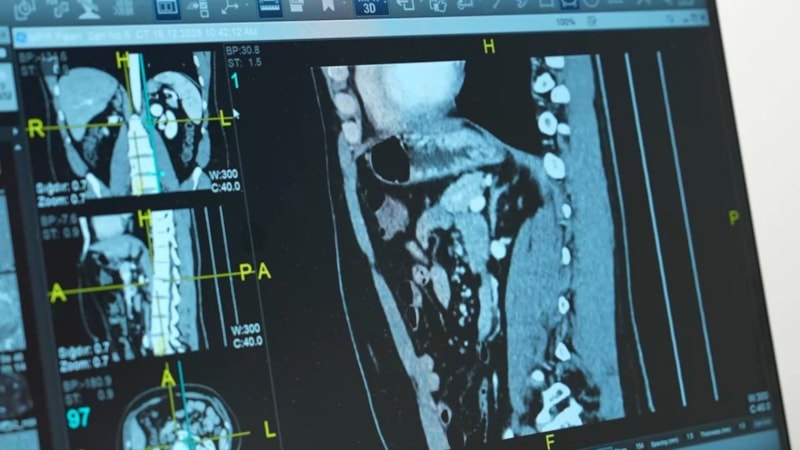

Metabolik hastalıkların sessizce çürüttüğü böbrek ve karaciğerler nedeniyle nakil listeleri hızla kabarıyor. Medipol Sağlık Grubu’ndan Organ Nakli Uzmanı Prof. Dr. Onur Yaprak, “Sadece yaşlılar değil, metabolik hastalıklar yüzünden gençler de organlarını kaybediyor.” diyerek acı tabloyu özetledi.

Organ yetmezliği, eskiden sadece ileri yaş veya doğuştan gelen hastalıklarla anılırdı. Ancak günümüzde obezite, diyabet ve hipertansiyon gibi metabolik hastalıkların yaygınlaşması, organ nakli ihtiyacını hiç olmadığı kadar artırdı.

Kadavradan organ bağışı hakkında toplumda yanlış bilgiler olduğuna dikkat çeken Prof. Dr. Yaprak, “Beyin ölümü; kalp krizi, kafa içi basıncı artıran hastalıklar ya da oksijensiz kalma gibi nedenlerle gelişebilir. Beyin ölümü gerçekleştiğinde kişi yoğun bakımda yaşam destek cihazlarına bağlı olur. Bu sırada organlar hala kanlanır ve çalışır. Bağış, bu aşamada ailenin onayıyla yapılır. Bu, bir cenazeden organ alınması değildir. Metabolik sendrom dediğimiz; diyabet, hipertansiyon, karaciğer yağlanması ve obezite gibi hastalıklar organlarımızı daha erken yaşta yıpratıyor. Bu da organ nakli ihtiyacını ciddi şekilde artırıyor. Organ bağışının hayati önem taşıyor.” ifadelerini kullandı.